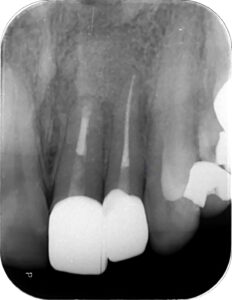

そこで、治療は長期に及ぶことを説明し、「根管治療による嚢胞の縮小」⇒「外科的歯内療法による嚢胞の完全摘出」の2段構えの戦略を立てました。

治療期間は1年数か月に及びましたが、液体が溜まっていた嚢胞内部には骨が再生し、現在は治療後の経過観察を行っています。

大切な前歯を抜歯することなく保存でき、患者様には大変喜んでいただきました。